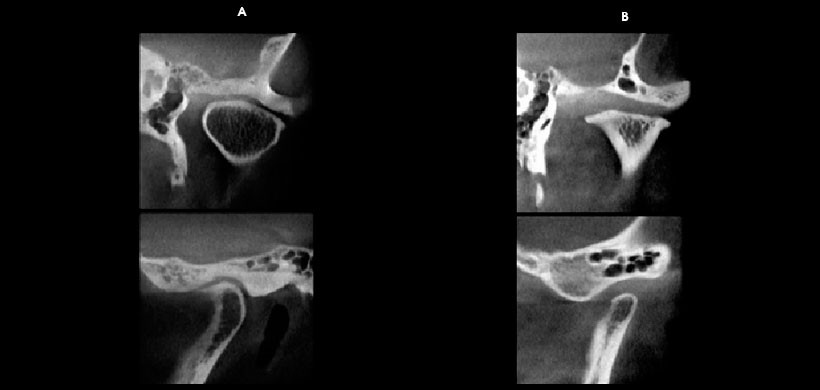

La mayor parte de los cambios morfológicos de las ATM observables en estudios tomográficos efectuados mediante la técnica cone beam, son producidos por procesos óseos degenerativos, derivados de la presencia de diversos grados de artrosis que pueden afectar esta articulación, los cuales generalmente se presentan en una secuencia que puede indicar en alguna medida, el grado de severidad del cuadro patológico. Estos son: engrosamiento de las corticales óseas articulares; y aplanamiento o facetación de las superficies óseas articulares, los primeros signos imagenológicos son considerados por muchos autores como cambios adaptativos de la ATM. A estos se le pueden agregar signos patológicos como erosiones de las corticales óseas articulares con compromiso del tejido óseo esponjoso subyacente, formación de osteofitos; presencia de “dobles corticales”; osteólisis avanzada de las superficies condilares, presencia de quistes subcondrales; y anquilosis de ATM. En muchos cuadros de artrosis de ATM estos signos imagenológicos se presentan en forma concurrente. Las alteraciones morfológicas de las ATM normalmente vienen además acompañadas de alteraciones posicionales y funcionales.